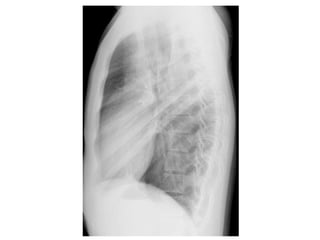

Usa-se o perfil com o

lado esquerdo próximo

do filme para evitar

que o coração seja

ampliado.

IDENTIFICAÇÃO DA RADIOGRAFIA

Pequenos derrames (50 ml) pleurais por demonstração de níveis

líquidos no espaço pleural.